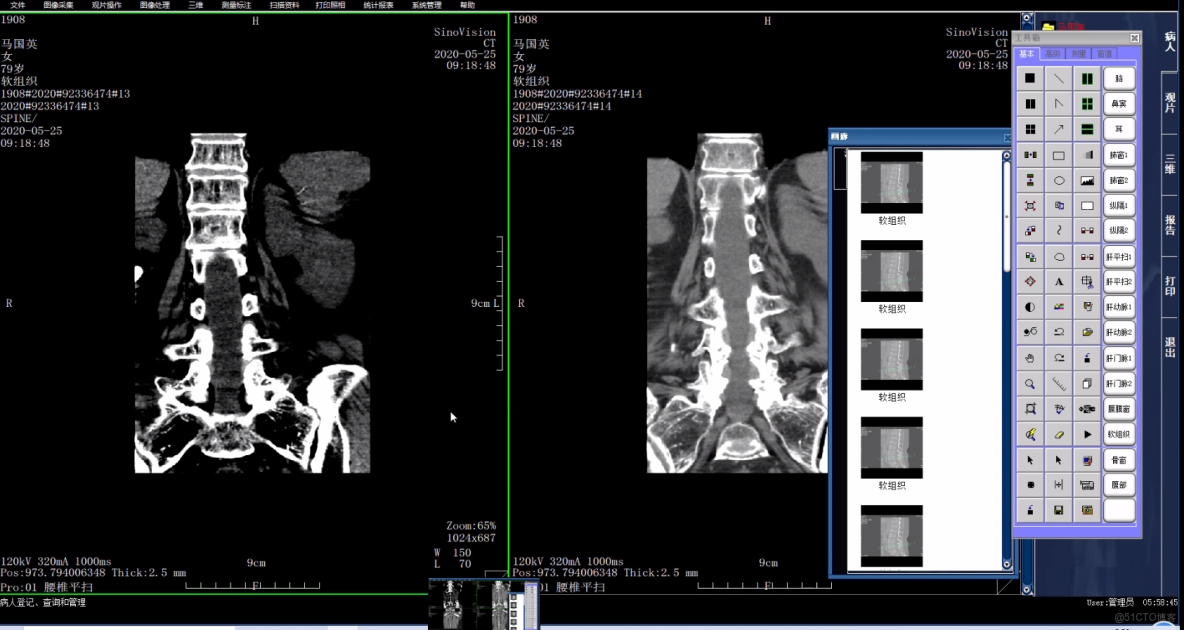

2、觀片工作站

醫學影像系統的核心組成部分,由影像醫技站調用,是醫生用於觀片診斷的平台,包括圖像觀察、圖像操作、圖像處理、圖像標註測量、報告處理、膠片打印(DICOM 打印)及高級影像處理等功能,用於指定病人的圖像診斷,也可作為獨立的應用系統單獨使用。

功能特色

自適應調窗,窗寬、窗位的調整

鼠標穿梭定位

三維鼠標

矢冠狀重建

序列間圖像同步

圖像直接輸出到PowerPoint

自定義觀片方式(圖像佈局和預設窗口)

圖像負相

圖像消隱

圖像的翻轉和旋轉

圖像漫遊

圖像縮放,放大鏡功能

圖像的多副本複製

圖像的偽彩處理

圖像濾波

血管狹窄測量

影像播放

測量CT值或MR值

封閉圖形內均植

CT曲線

DICOM打印

圖像拼接

圖像平滑處理

圖像鋭化處理

DSA數字減影